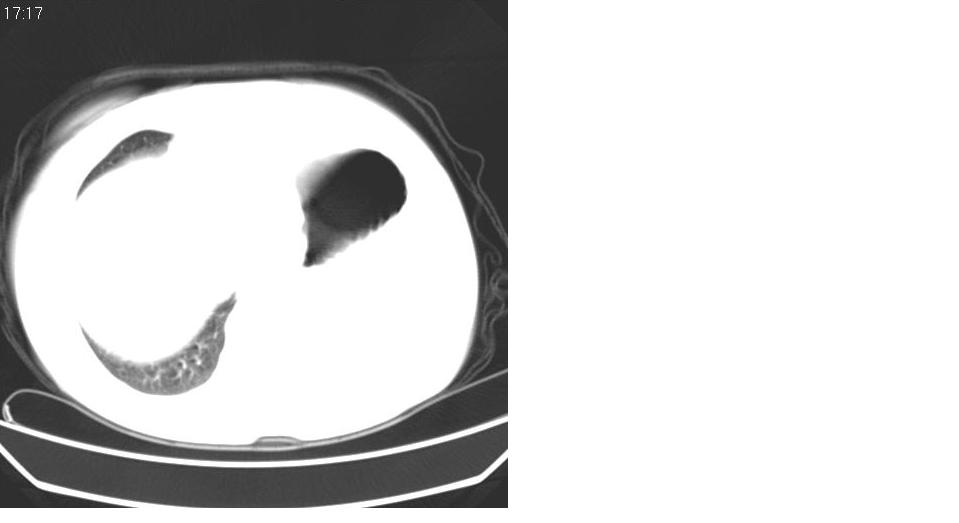

女 59岁,胸背疼,不咳嗽,不咳痰,不发热。

1)考虑左肺下叶背段周围型肺癌并左肺下叶及左侧胸膜转移。2)左侧胸腔积液。3)左冠状动脉钙化。

支持楼上,左侧膈肌抬高,考虑膈疝或膈麻癖可能。

1)考虑左肺下叶背段周围型肺癌并左肺下叶及左侧胸膜转移。2)左侧胸腔积液。

1)考虑左肺下叶背段周围型肺癌(腺癌可能性大)并左肺下叶及左侧胸膜转移。2)左侧胸腔积液。3)左冠状动脉钙化。